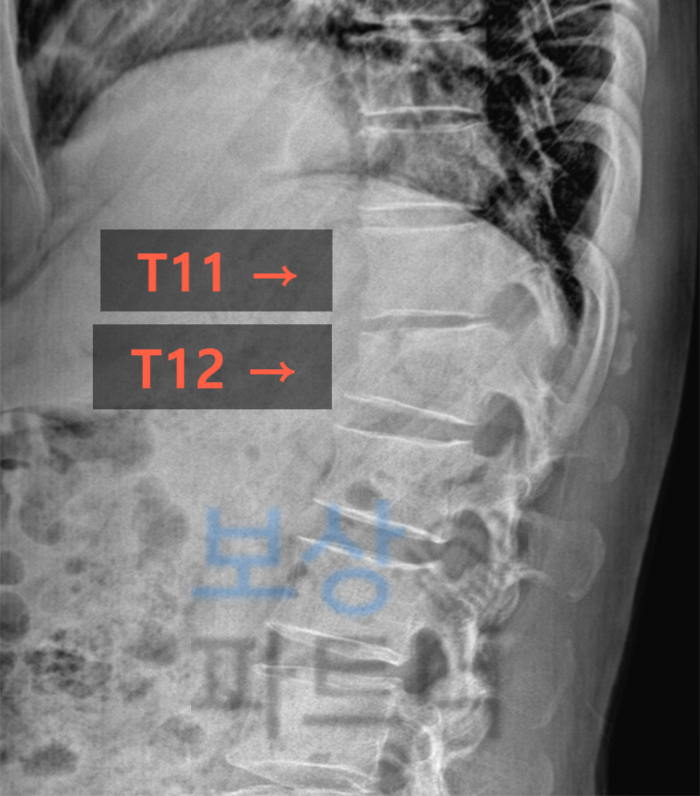

오늘은 교통사고로 흉추 T11, T12 골절되셨던 고객의 성공적인 합의금 사례 소개해 드리겠습니다. 충북에 거주하시는 50대인 의뢰인께서는 도로 주행 중에 상대방 차량과 추돌하는 교통사고를 당하셨습니다.

이 사고로 환자분께서는 흉추 11번, 12번 골절되셨는데요. 그중 흉추 11번(T11)은 척추체가 아닌 횡돌기 골절이기에 비교적 경미한 상태였습니다. 하지만 흉추 12번(T12)은 X-ray 영상으로도 그 높이가 낮게 주저앉은 것이 확인이 되는데요.

즉 이것은** 압박골절**의 양상을 띠면서 영구적인 변형을 가져오게 됩니다.